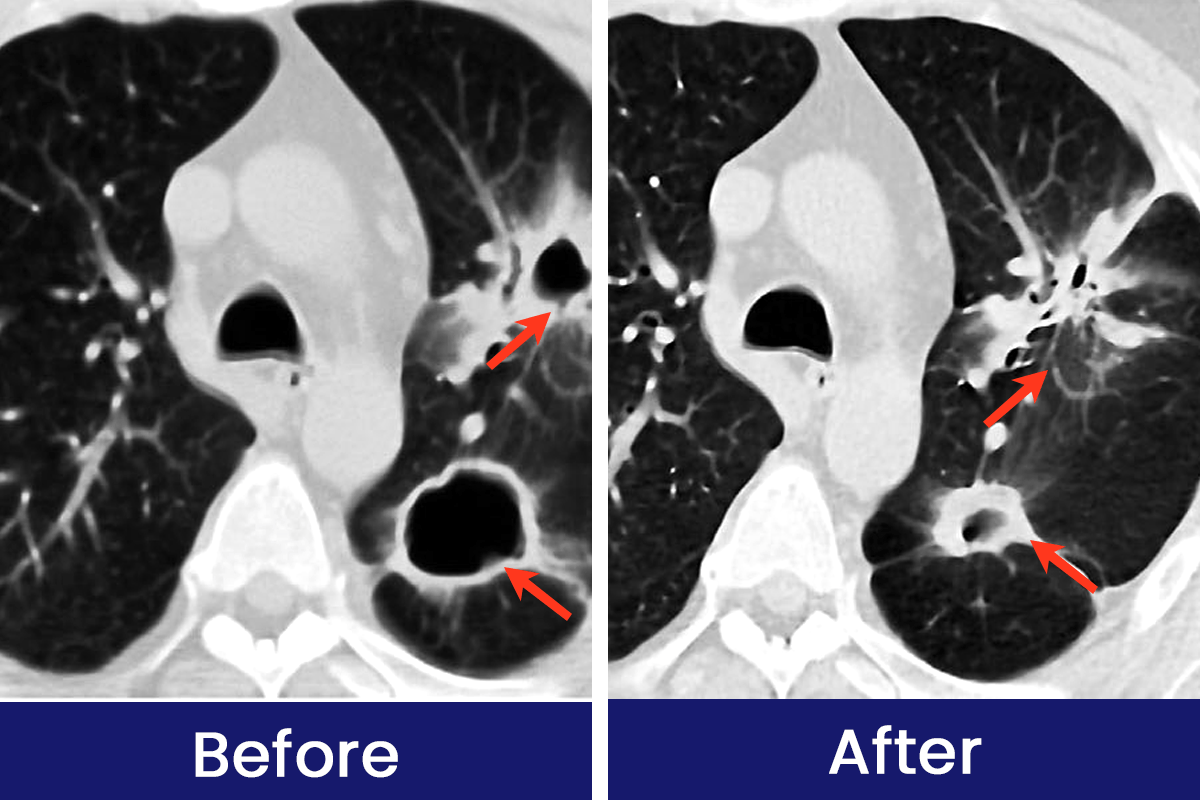

See How Luhaka™ Nicofree is Helping Customers Breathe Easier and Live Smoke-Free Every Day!